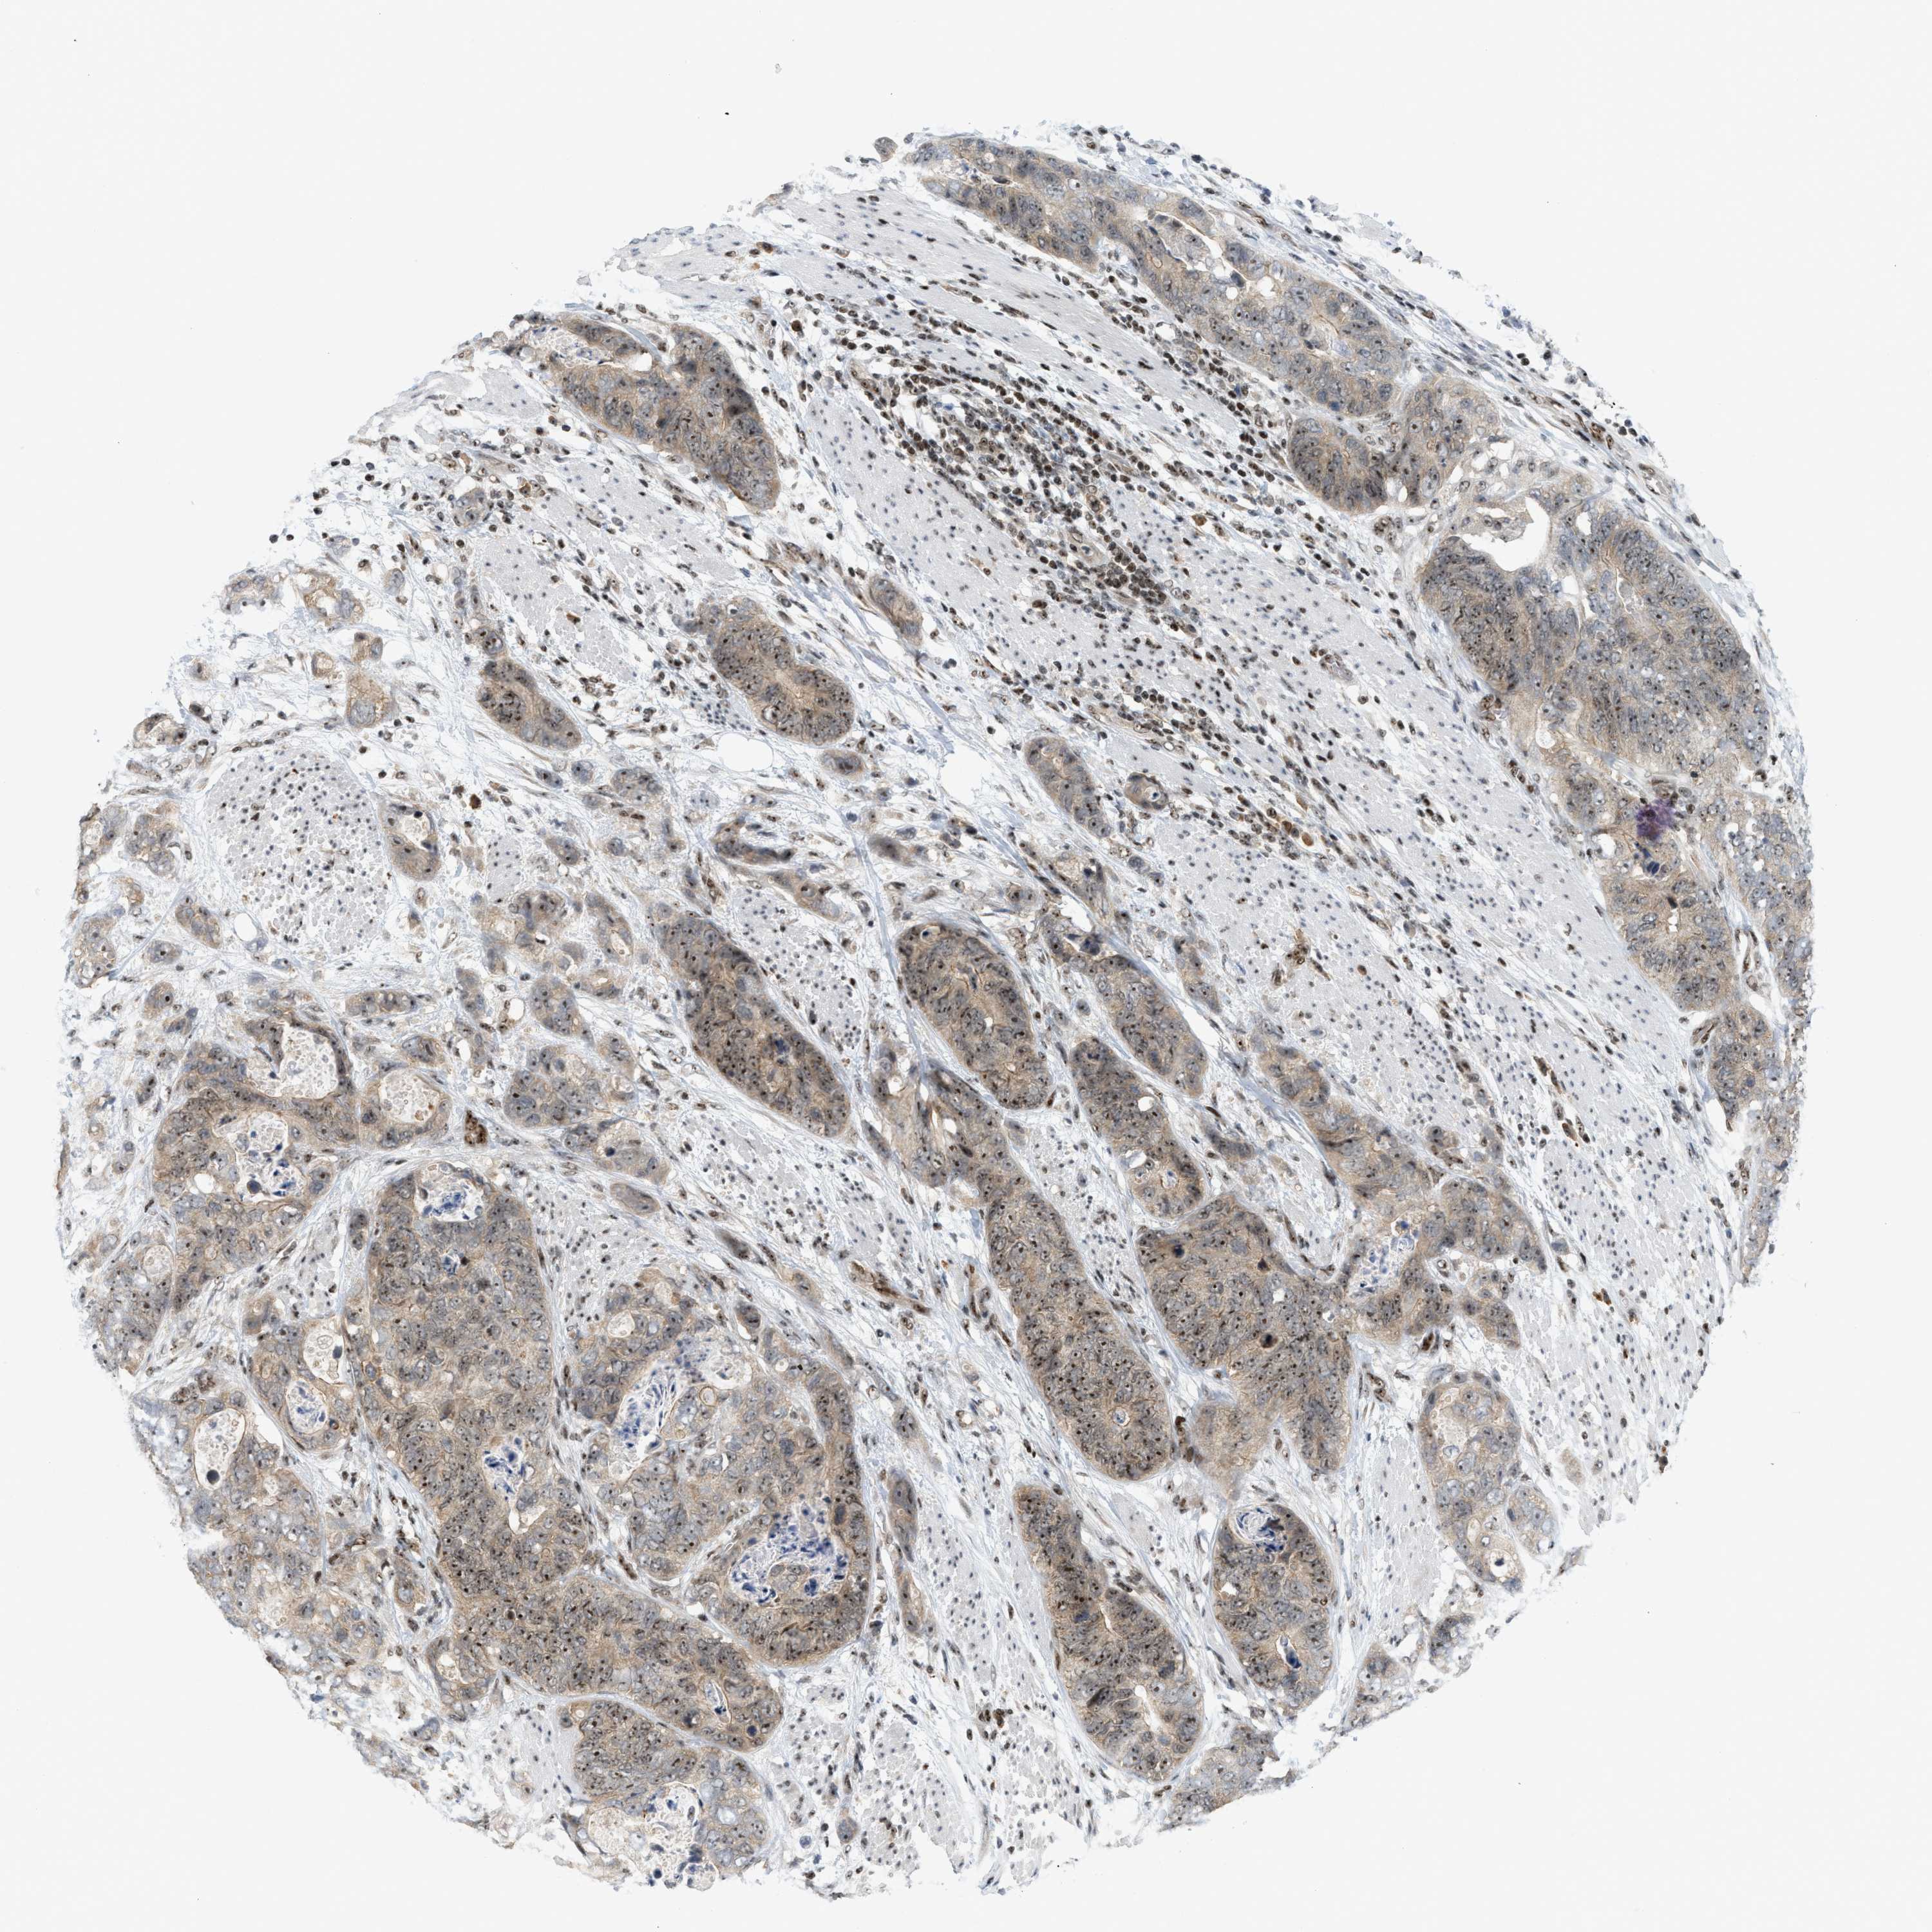

STOMACH CANCER - Protein expressioni

A mouse-over function shows sample information and annotation data. Click on an image to view it in a full screen mode. Samples can be filtered based on level of antibody staining by selecting one or several of the following categories: high, medium, low and not detected. The assay and annotation is described here.

Note that samples used for immunohistochemistry by the Human Protein Atlas do not correspond to samples in the TCGA dataset.

Antibody stainingi

Antibody staining in the annotated cell types in the current human tissue is reported as not detected, low, medium, or high, based on conventional immunohistochemistry profiling in selected tissues. This score is based on the combination of the staining intensity and fraction of stained cells.

Each image is clickable and will lead to virtual microscopy that enables deeper exploration of all samples and also displays staining intensity scores, fraction scores and subcellular localization as well as patient and tissue information for each sample.

Antibody HPA016736

Staining

High

Medium

Low

Not detected

Intensity

Strong

Moderate

Weak

Negative

Quantity

>75%

75%-25%

<25%

None

Location

Nuclear

Cytoplasmic/membranous

Cytoplasmic/membranous,nuclear

Adenocarcinoma, NOS